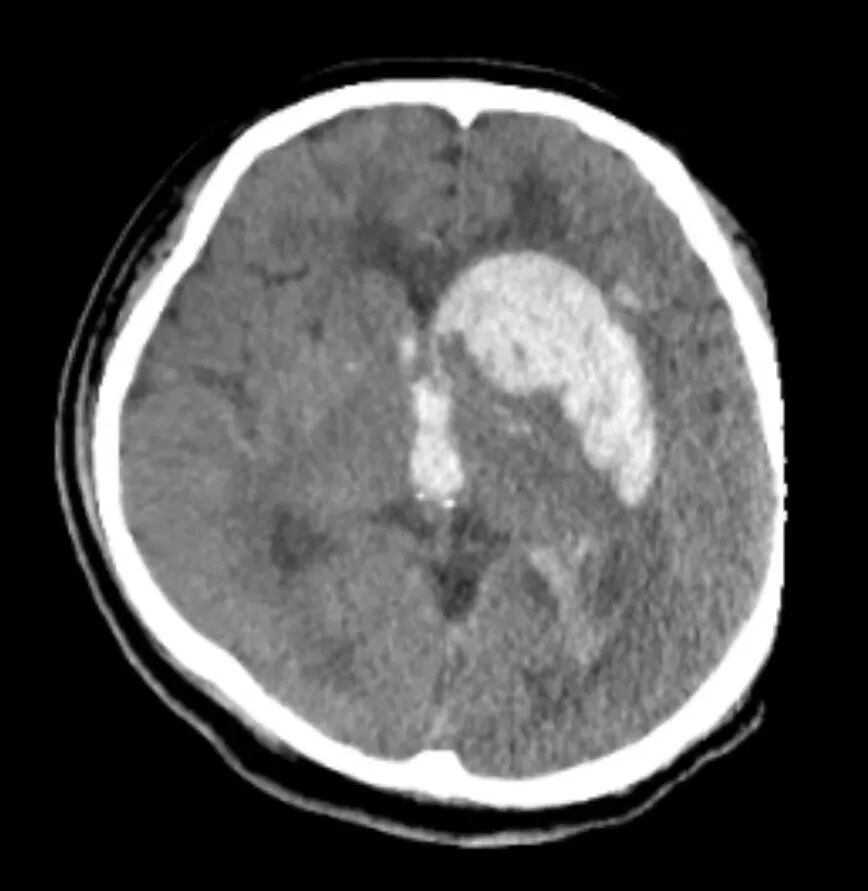

该患者的术前颅脑CT检查。

据悉,该患者患有高血压,但未规范控制。前几天的一个晚上,突发头痛,言语不清,右侧肢体无力,继而昏迷。此后,他被工友紧急送到了烟台山医院东院区。该患者为外来务工人员,单身,经济条件较差,但病情危重,不容等待,医院及时开通“绿色通道”。经查,该患者患有高血压脑出血,脑疝前期,此后被收住到外科重症监护病房。